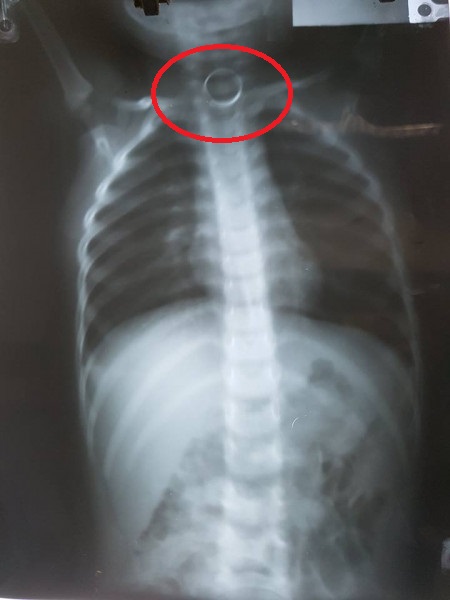

Ngay sau khi tiếp nhận bệnh nhi, các bác sĩ đã tiến hành chụp X-quang. Kết quả cho thấy, trong thực quản bé có dị vật hình tròn, đường kính khoảng 2cm, nằm ở thực quản ngang đốt sống cổ số 6-7. Bác sĩ trực đề nghị chuyển bé xuống BV tuyến trên ở Hà Nội do BV không thiết bị kĩ thuật phù hợp để nội soi cho bệnh nhi.

Trong điều kiện không có ống nội soi cho trẻ, kìm để gắp dị vật đã hỏng, kíp trực gồm các bác sĩ Tai - Mũi – Họng, gây mê phẫu thuật đã hội chẩn, gây mê và nội soi để gắp dị vật ra khỏi thực quản bệnh nhi. Dị vật được lấy ra an toàn là chiếc vòng móc khoá.